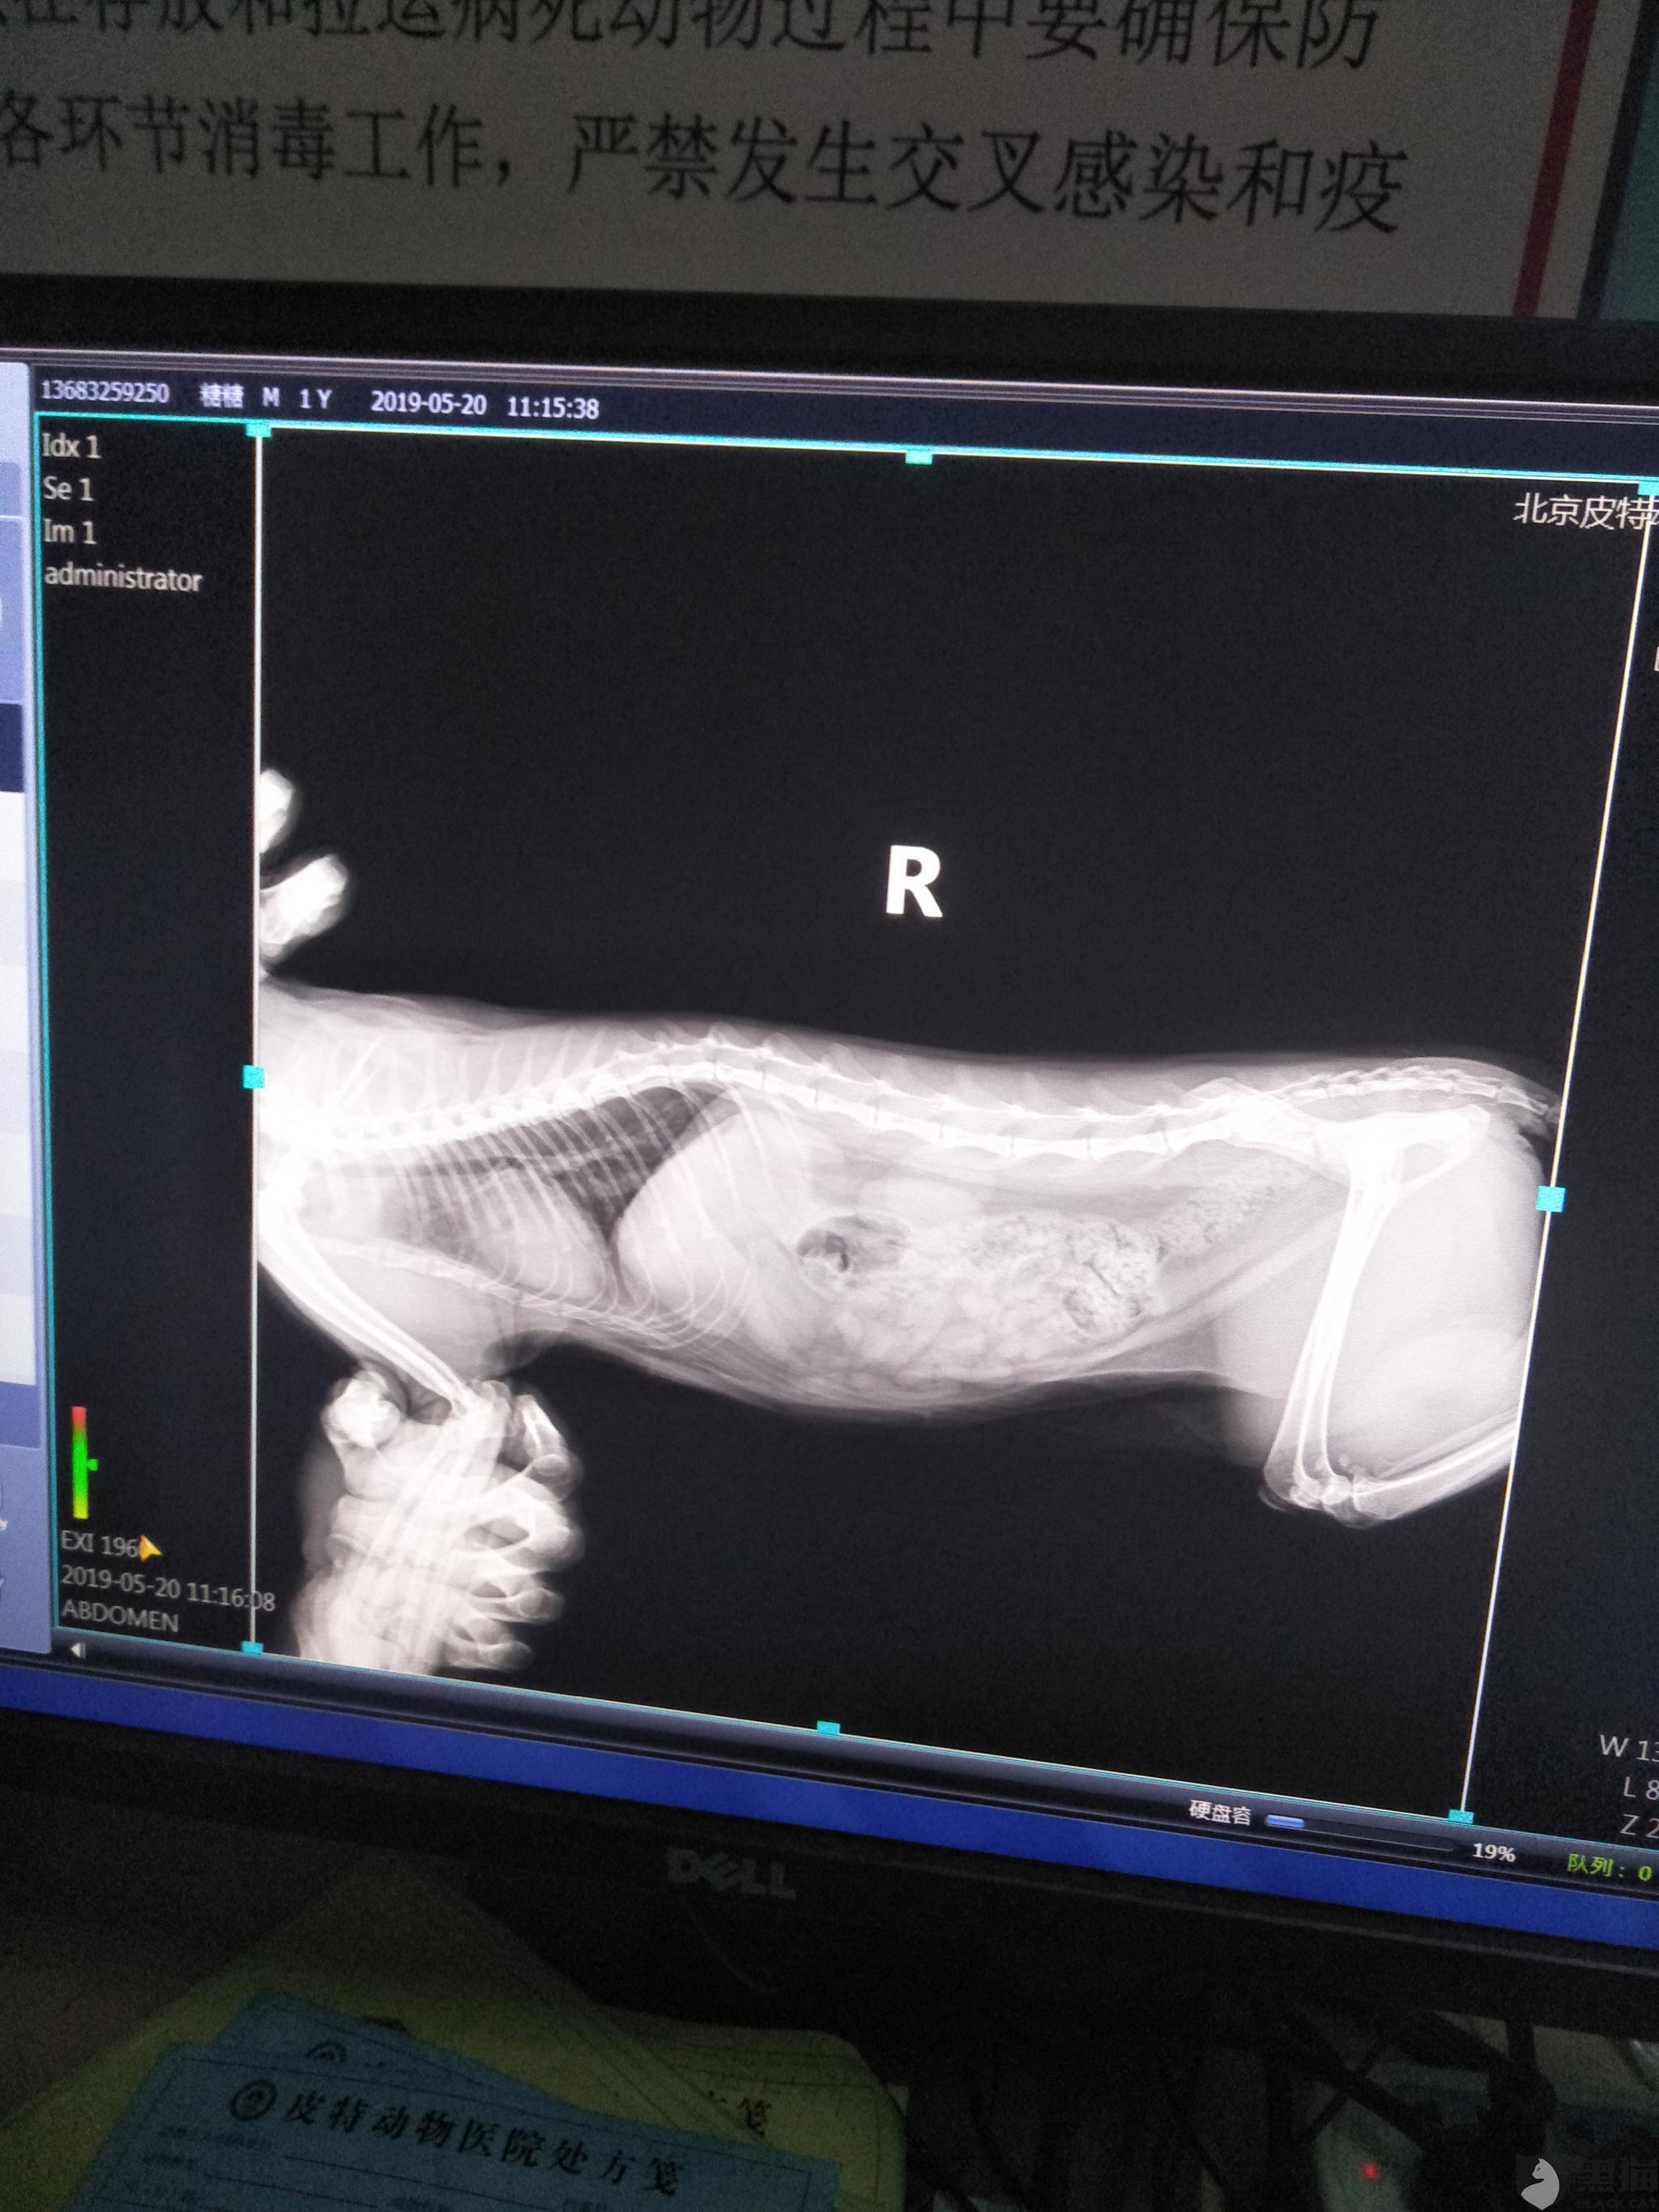

母猫肚子还很大,去宠物医院b超诊断,肚子里还有三只小猫,不过也死了.

猫咪怀孕40天b超图片

猫咪怀孕20天b超图片

猫咪b超图

猫B超